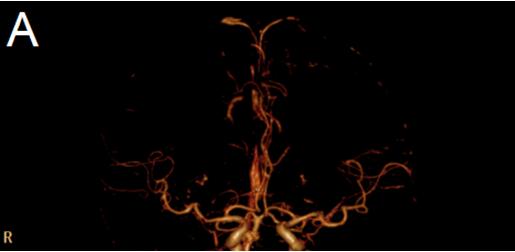

我院为患者立即开通卒中绿色通道,急查头颅DWI:右侧基底节、半卵圆中心、颞叶内侧、顶枕叶皮层多发急性梗塞灶,头部CTA显示右侧大脑中动脉M1段闭塞(图1);头部CT未见急性出血灶。诊断:“1.急性脑梗死;2.右侧大脑中动脉闭塞;3.高血压病2级 极高危组”明确。

图1 A:头颅CTA显示右侧大脑中动脉M1段闭塞(2017/9/6 18:38)

患者出院后1个月来我院复查,行走自如,活动灵活,无明显不适,神经系统未见阳性体征。NIHSS:0分。查头颅CTA对比PACS图像(2017-9-6 头颈部CTA),现:原右侧大脑中动脉M1段起始段闭塞已缓解、局部变细,远端分支明显减少较前缓解(图3)。

图3 A:1月后复查头颅CTA显示右侧大脑中动脉M1段起始段闭塞已缓解、局部变细,远端分支明显减少较前缓解。